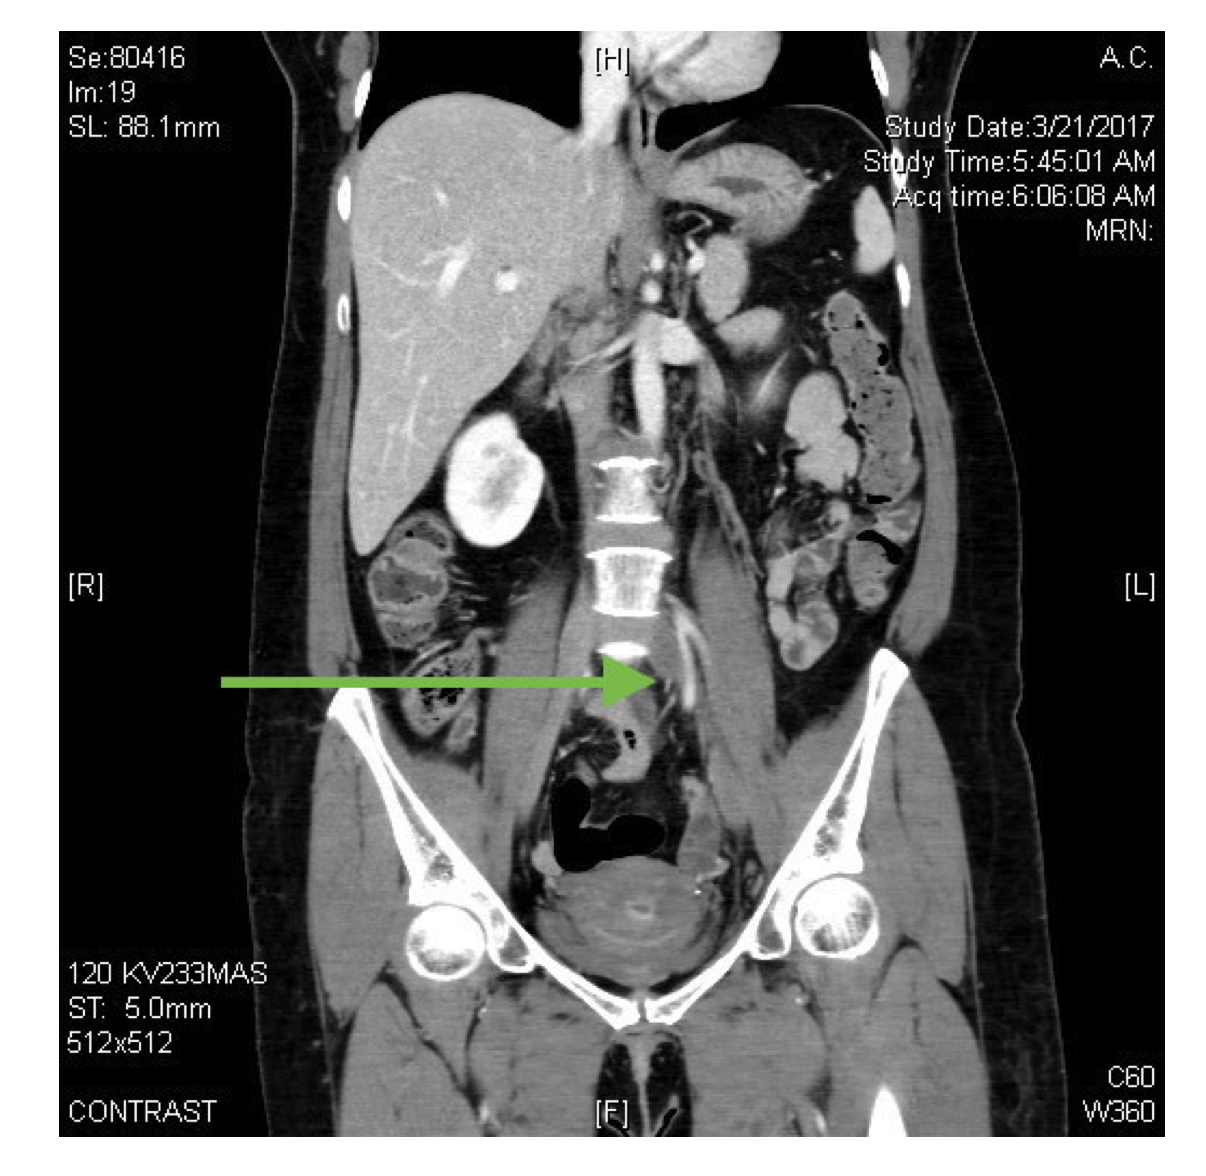

In the CTA abdomen/pelvis image below, the single coronal image arrow is placed to demonstrate the bifurcation of the distal aorta into the right and left iliac arteries. This “V” shape is seen with hyperdense contrast enhancing the vessels. These are the proximal iliac arteries, and thus the right iliac artery is still positioned on the left side of the body but will soon cross midline. Immediately inferior to the hyperdense right iliac artery, compression of the left common iliac vein is visualized with likely clot within the vessel.

May-Thurner Syndrome, also known as Iliac Vein Compression Syndrome, occurs when the common iliac vein is compressed by an overlying common iliac artery. Typically, the left common iliac vein is compressed by the right common iliac artery1-3. In the photo below, the aorta descends along the left lateral side of the inferior vena cava, and then its terminal branch crosses on top of (and sometimes compresses) the left terminal branch of the inferior vena cava against the lumbar spine3. This compression can lead to discomfort, decreased venous return, and ultimately deep venous thrombosis (DVT)1,3. As the DVT initiates at a proximal location in the lower extremity, the thrombus can be very large and propagate quickly3.